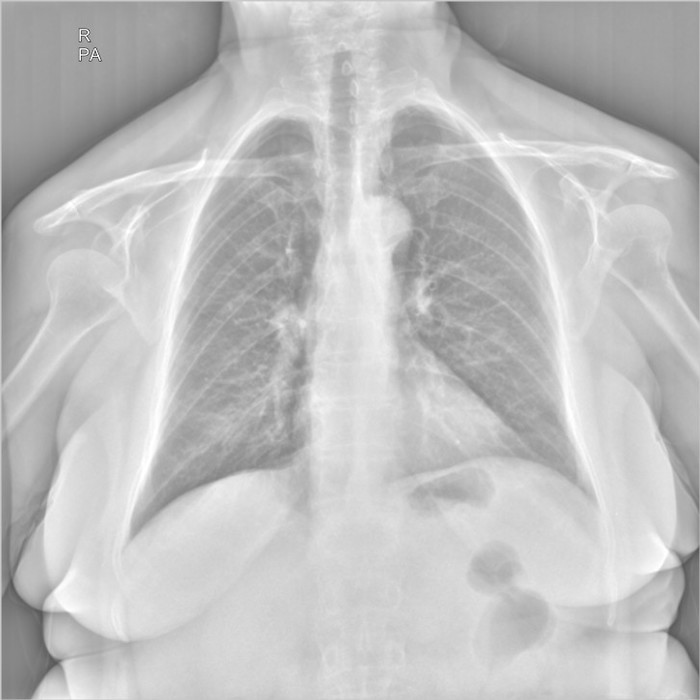

Здравствуйте, я работаю лаборантом в рентген кабинете, в госпитале, в Ливий. К сожалению у нас нет рентгенолога, и в некоторый случаях мне приходиться "читать" снимки самому... Со мной вместе работает мама, она медсестра в реанимаций. Ей сейчас 67 лет, решил сделать ей рентген лёгких, на боли в груди она не жалуется. Я начал изучать снимок и увидел образование в форме круга в левом легком возле бронха, подскажите мне пожалуйста что это такое и стоит ли мне беспокоится. Фото в негативе и позитиве прилагаю ниже.